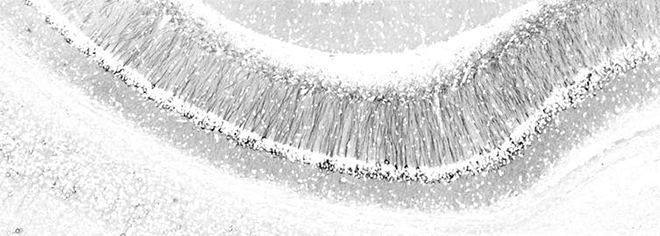

Neurons in the hippocampus

Neurons in the hippocampus Amandine Grimm/QBI

The organisation of neurons in the hippocampus, a brain region important for learning and memory, looks like a forest in snow. The “snow” is made of cell nuclei, which contain each cell’s genetic material. The “trees” are the neurons’ projections, along which electrical signals travel to enable communication with other cells.